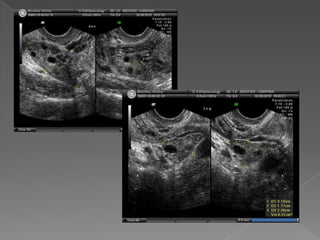

• 25.

 Visibles acada lado del útero  Reparo: vasos ilíacos  Móviles, posición variable  Estructuras ovoideas , hipoecogénicas, porción central mas ecogénica  Tamaño : 3 cm x 2 cm x 2cm  Volumen : L x AP x T x 0.523  Vol. : 6 a 10 cm cúbicos , max :14 -16  Folículos : fácil identificación  Miden de 2 a 25 mm de diámetro